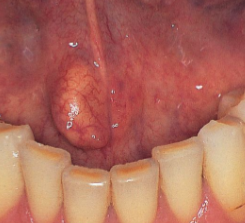

cheilitis glandularis

rare inflammatory condition of minor salivary glands

lower lip

openings of ducts are dilated and inflamed

cheilitis glandularis image